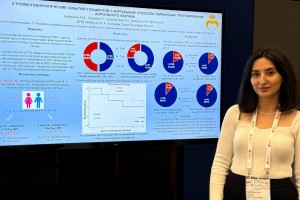

Участие сотрудников лаборатории в конгрессах

Сотрудники НИЛ ежегодно принимают участие в российских и международных кардиологических конгрессах.  В 2019 году Сефиева Г.Г. успешно выступила на Европейском конгрессе кардиологов в Париже с докладом «Изучение и оценка выживаемости беременных женщин с легочной гипертензией в зависимости от тяжести и этиологии данного заболевания». В 2021 году Сефиева Г.Г. выступила на Европейском конгрессе кардиологов с докладом «Тромботические и геморрагические осложнения при беременности, родах и в послеродовом периоде у женщин с протезами клапанов сердца». В 2022 году Сефиева Г.Г. выступила на Российском конгрессе кардиологов с докладом «Тактика антикоагулянтной терапии и тромбогеморрагические осложнения у женщин с механическими клапанами сердца в послеродовом периоде».

В 2019 году Сефиева Г.Г. успешно выступила на Европейском конгрессе кардиологов в Париже с докладом «Изучение и оценка выживаемости беременных женщин с легочной гипертензией в зависимости от тяжести и этиологии данного заболевания». В 2021 году Сефиева Г.Г. выступила на Европейском конгрессе кардиологов с докладом «Тромботические и геморрагические осложнения при беременности, родах и в послеродовом периоде у женщин с протезами клапанов сердца». В 2022 году Сефиева Г.Г. выступила на Российском конгрессе кардиологов с докладом «Тактика антикоагулянтной терапии и тромбогеморрагические осложнения у женщин с механическими клапанами сердца в послеродовом периоде».

В сентябре 2023 года Бабакехян М.В. представила постерный доклад по теме «Клинические особенности течения фибрилляции предсердий у больных с аортальным стенозом» на Юбилейном Российском национальном конгрессе кардиологов, городе Москва.